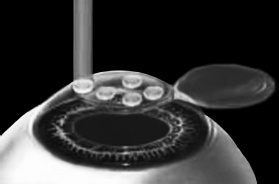

Рис. 6. Луч эксимерного лазера испаряет на роговичном ложе несколько микрон стромы роговицы.

Иллюстрация с сайта Международного лазерного центра www.optics.ru

Стоит один раз моргнуть и лоскут скомкается и зрения не будет. Его бы пришить на место. Но швы деформируют роговицу. Все проще. Лоскут разглаживают мокрым тупфером, прижимая его ровненько к старому месту (рис. 7 и 8). Только место не старое, с роговичного ложа удалили несколько микрон в виде причудливой ямки (при коррекции близорукости).

Рис. 7. При коррекции близорукости на роговичном ложе формируется «ямка».